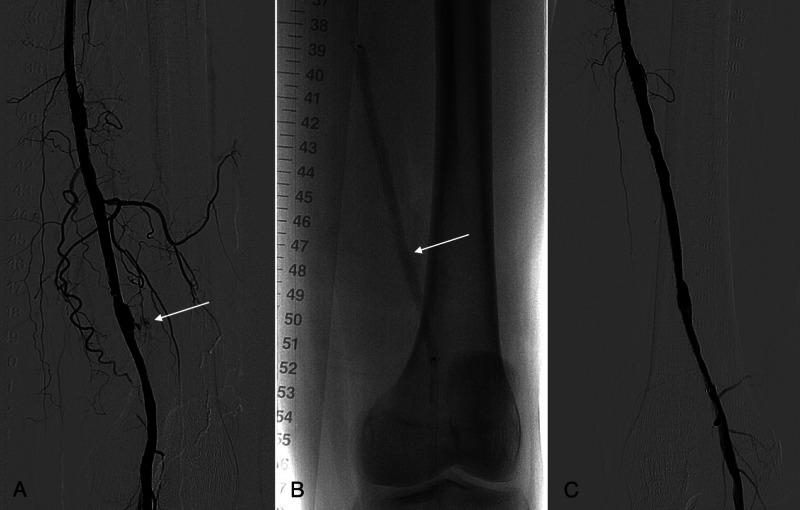

Superficial Femoral Artery Pseudoaneurysm and Arterial Wall Destruction After Drug-Coated Balloon Treatment.

Drug-coated balloon angioplasty may present an efficient alternative to traditional balloon angioplasty and stenting, which suffer from high rates of restenosis and increased risk of stent fractures in the anatomically unfavorable regions, such as the superficial femoral artery in the adductor canal. Although pseudoaneurysms are the most common vascular access site complications, they are considerably rarer at the site of the endovascular treatment. They can be caused by several mechanisms, including stent fractures, usage of oversized balloons, high-pressure inflations, and infections. In addition, paclitaxel, the drug released from drug-coated balloons, may also play a significant role in the formation and exacerbation of pseudoaneurysms. The exact pathophysiology remains unclear, but it may be due to a combination of paclitaxel's suppression of neointimal healing and immune response, cytotoxic properties, and hypersensitivity-related inflammation.